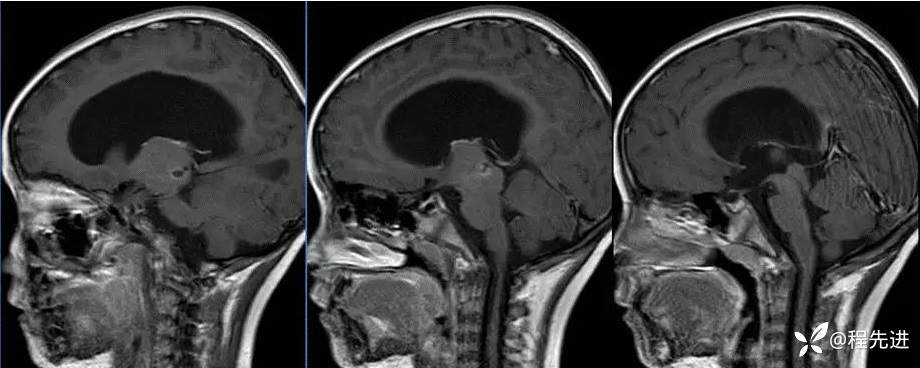

MR